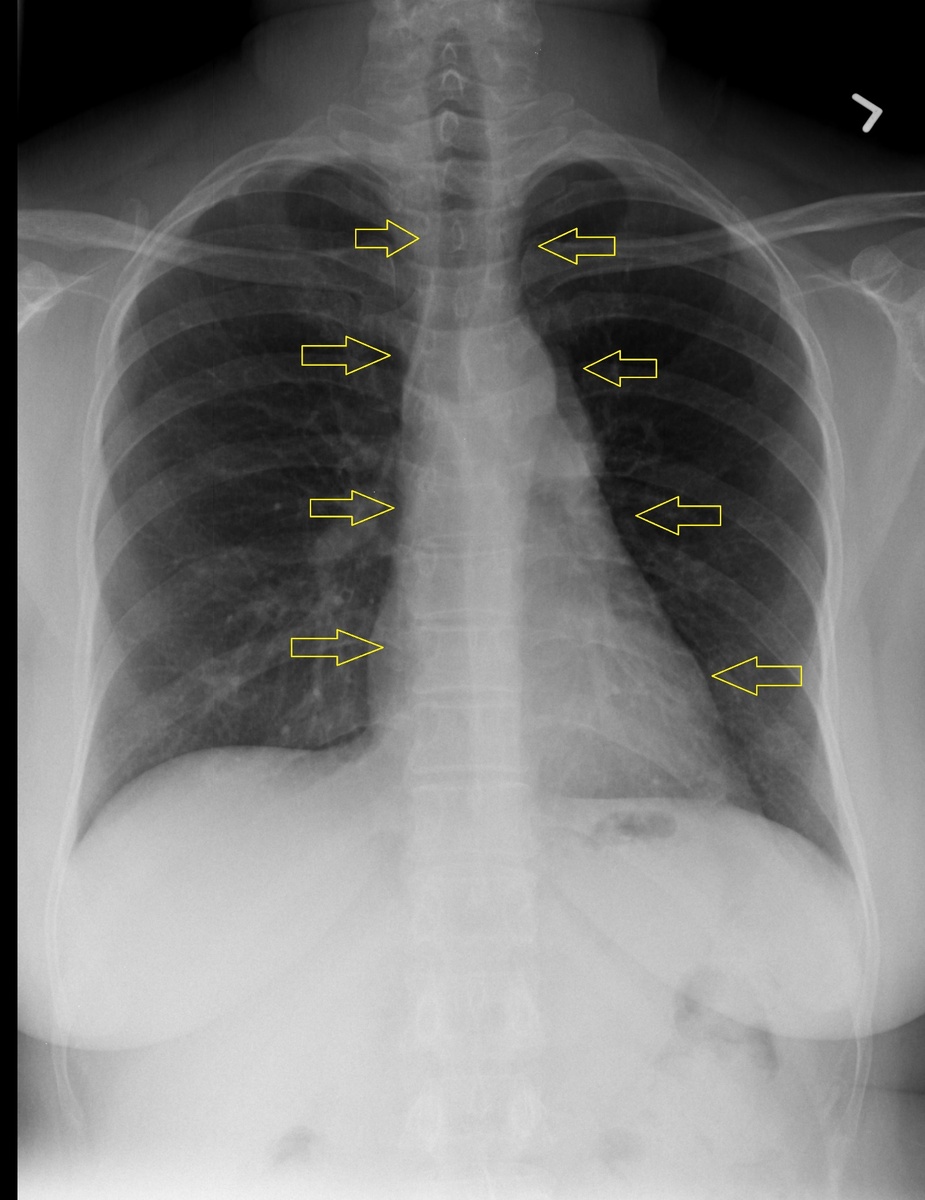

Как диагностировать образование переднего средостения? Либо рентген, но есть очень большая вероятность, что образование малых размеров увидеть не получится, либо КТ ОГК. Последняя намного информативнее.

Вот, например, стрелками показано средостение. Найти тут опухоль достаточно сложно, т. к. изображение накладывается одно на другое (трахея накладывается на аорту, аорта на пищевод и т.д.)

Рентген